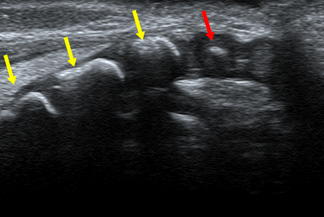

Texto alternativo para a imagem Figura 1. Créditos: Dra. Elazir Mota - Rio de Janeiro/RJ

Descrição da figura 1: Ultrassonografia da coluna lombossacra evidenciando as peças sacrais (já ossificadas - setas amarelas), e a primeira peça coccígea iniciando seu processo de ossificação (seta vermelha).